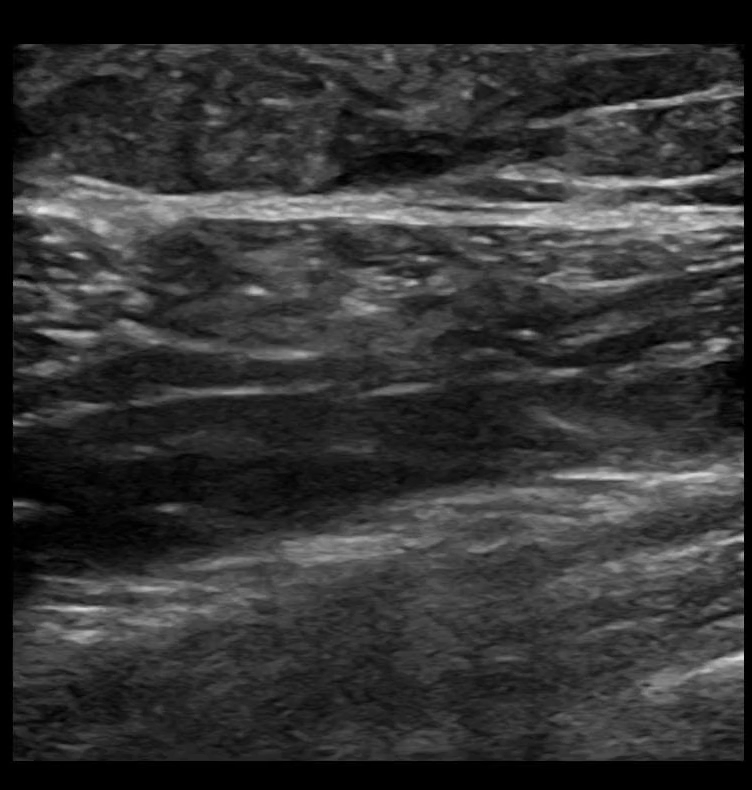

SAPB 6: The ability to follow your needle tip in long axis is an absolute necessity, because deep to the serratus anterior muscle lies rib and pleura.

SAPB 8: Needle in long axis being removed. Visualization of needle tip is maintained throughout the entire procedure.